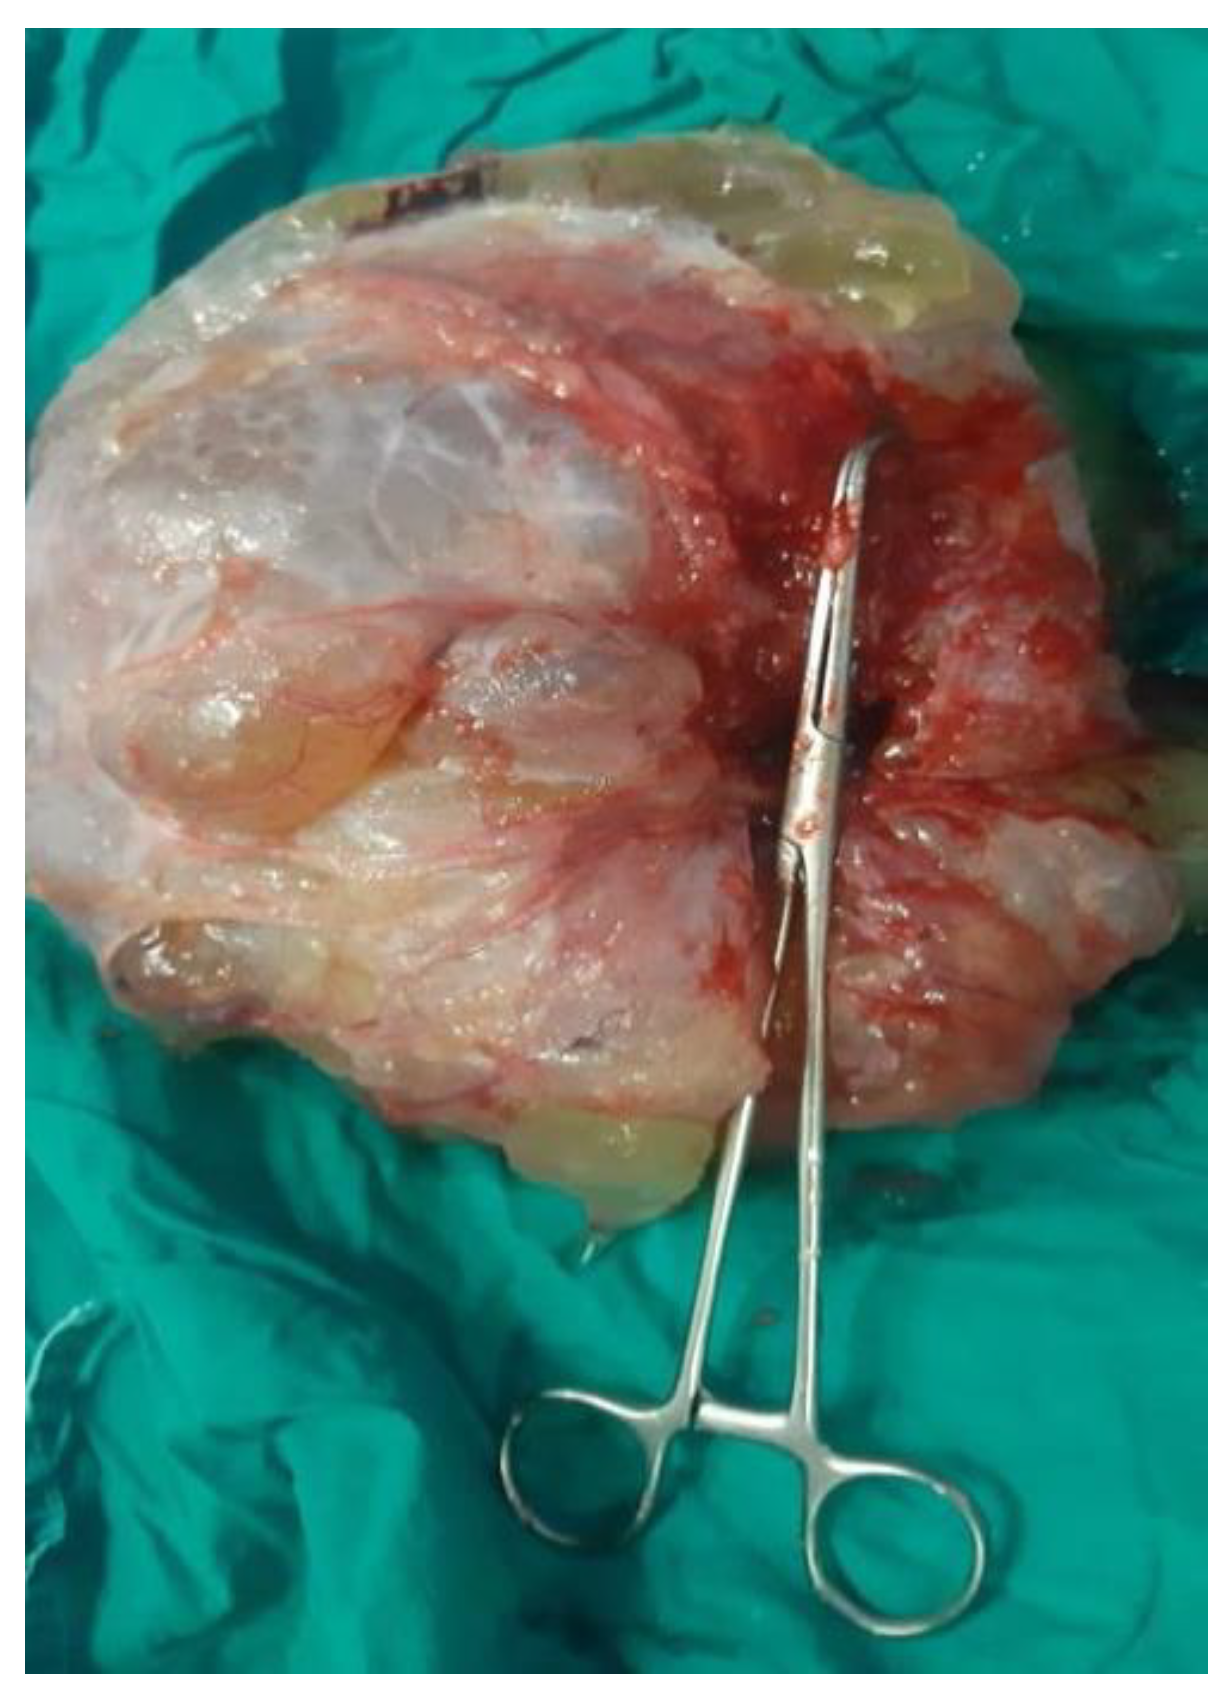

3.1.1. Mucinous Cystadenoma

- Purwoto, G.; Anggraeni, T.D.; Rustamadji, P.; Surya, I.U.; Julianti, K.; Herlambang, N. Histopathological discrepancy and variation of surgical management in mucinous ovarian cystadenoma and pseudomyxoma peritonei. Int. J. Surg. Case Rep. 2022, 94, 107141. [Google Scholar] [CrossRef] [PubMed]

- Tjokroprawiro, B.A.; Nugroho, H.; Indraprasta, B.R. Huge and Unique Pseudomyxoma Peritonei. J. Obstet. Gynecol. India 2022, 72, 268–269. [Google Scholar] [CrossRef]